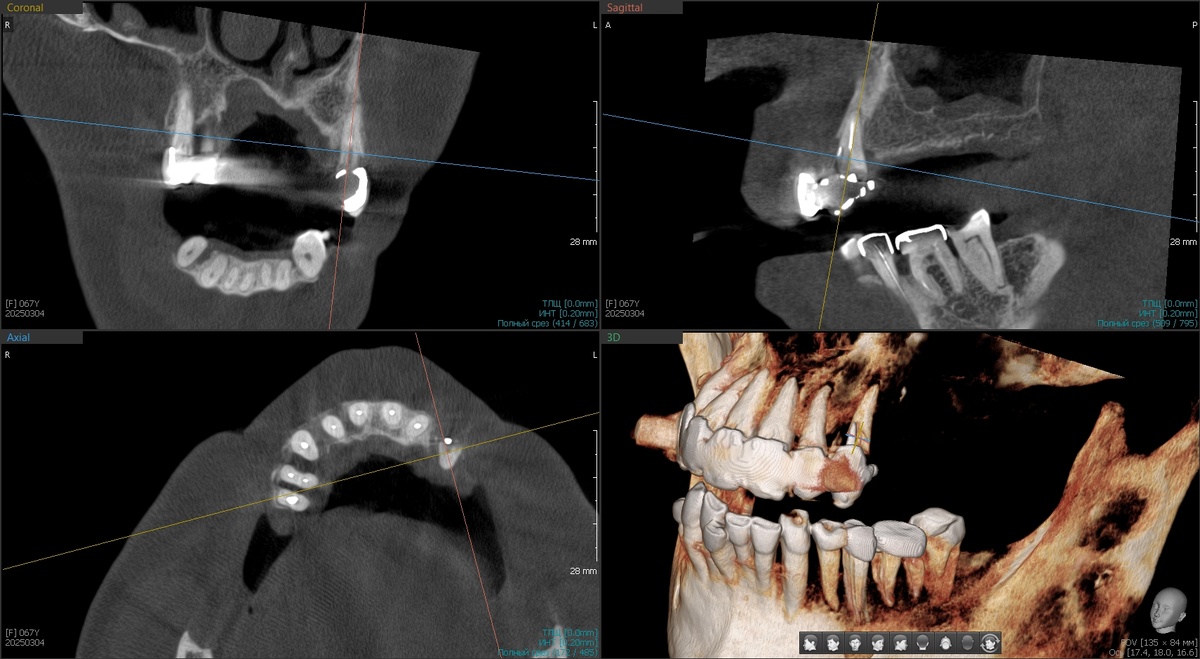

Решили действовать планомерно. В апреле 2025 года - первый этап.

Установили 2 птеригоидных имплантата и 2 классических имплантата на нижнюю челюсть в области 4.5 и 4.6 зубов.

Что такое птеригоидные имплантаты, помните? Это специальные длинные имплантаты, которые фиксируются в крыловидном отростке клиновидной кости черепа. Эта кость плотная и, практически, не подвержена атрофии даже при длительном отсутствии зубов. Птеригоидные имплантаты позволяют избежать синус-лифтинга - наращивания кости в гайморовой пазухе.

Дали время на приживление, отдохнуть от нас. Шесть месяцев ожидания - и вот, сентябрь 2025 года, новая встреча в плановом порядке.

Тотальная операция на верхней челюсти "All-on-4"

Оценили приживление апрельских имплантатов - все четыре интегрировались отлично (фото чуть ниже приложу). Можно приступать к основной работе.

1. Программа максимум - удаление всех оставшихся зубов верхней челюсти с распилом МК-моста (та ещё работёнка, стёрли несколько специальных боров в 0), установка 4 имплантатов по системе "All-on-4", отличные торки на всех имплантатах, немедленная нагрузка предвременным протезом (хлипким, он нужен для формирования контура десны для природоподобия).

2. Второй этап в тот же день - удаление зуба 4.4 на нижней челюсти, одномоментная установка имплантата, раскрытие двух апрельских имплантатов и мягкотканная пластика.

Программа максимум выполнена с апреля по сентябрь - установлено 6 имплантатов на верхней челюсти, 3 имплантата на нижней, мягкотканная пластика, предвременный протез в день операции. Всё, что планировали, случилось без эксцессов. Птеригоидные имплантаты прижились идеально, основная операция прошла без осложнений.